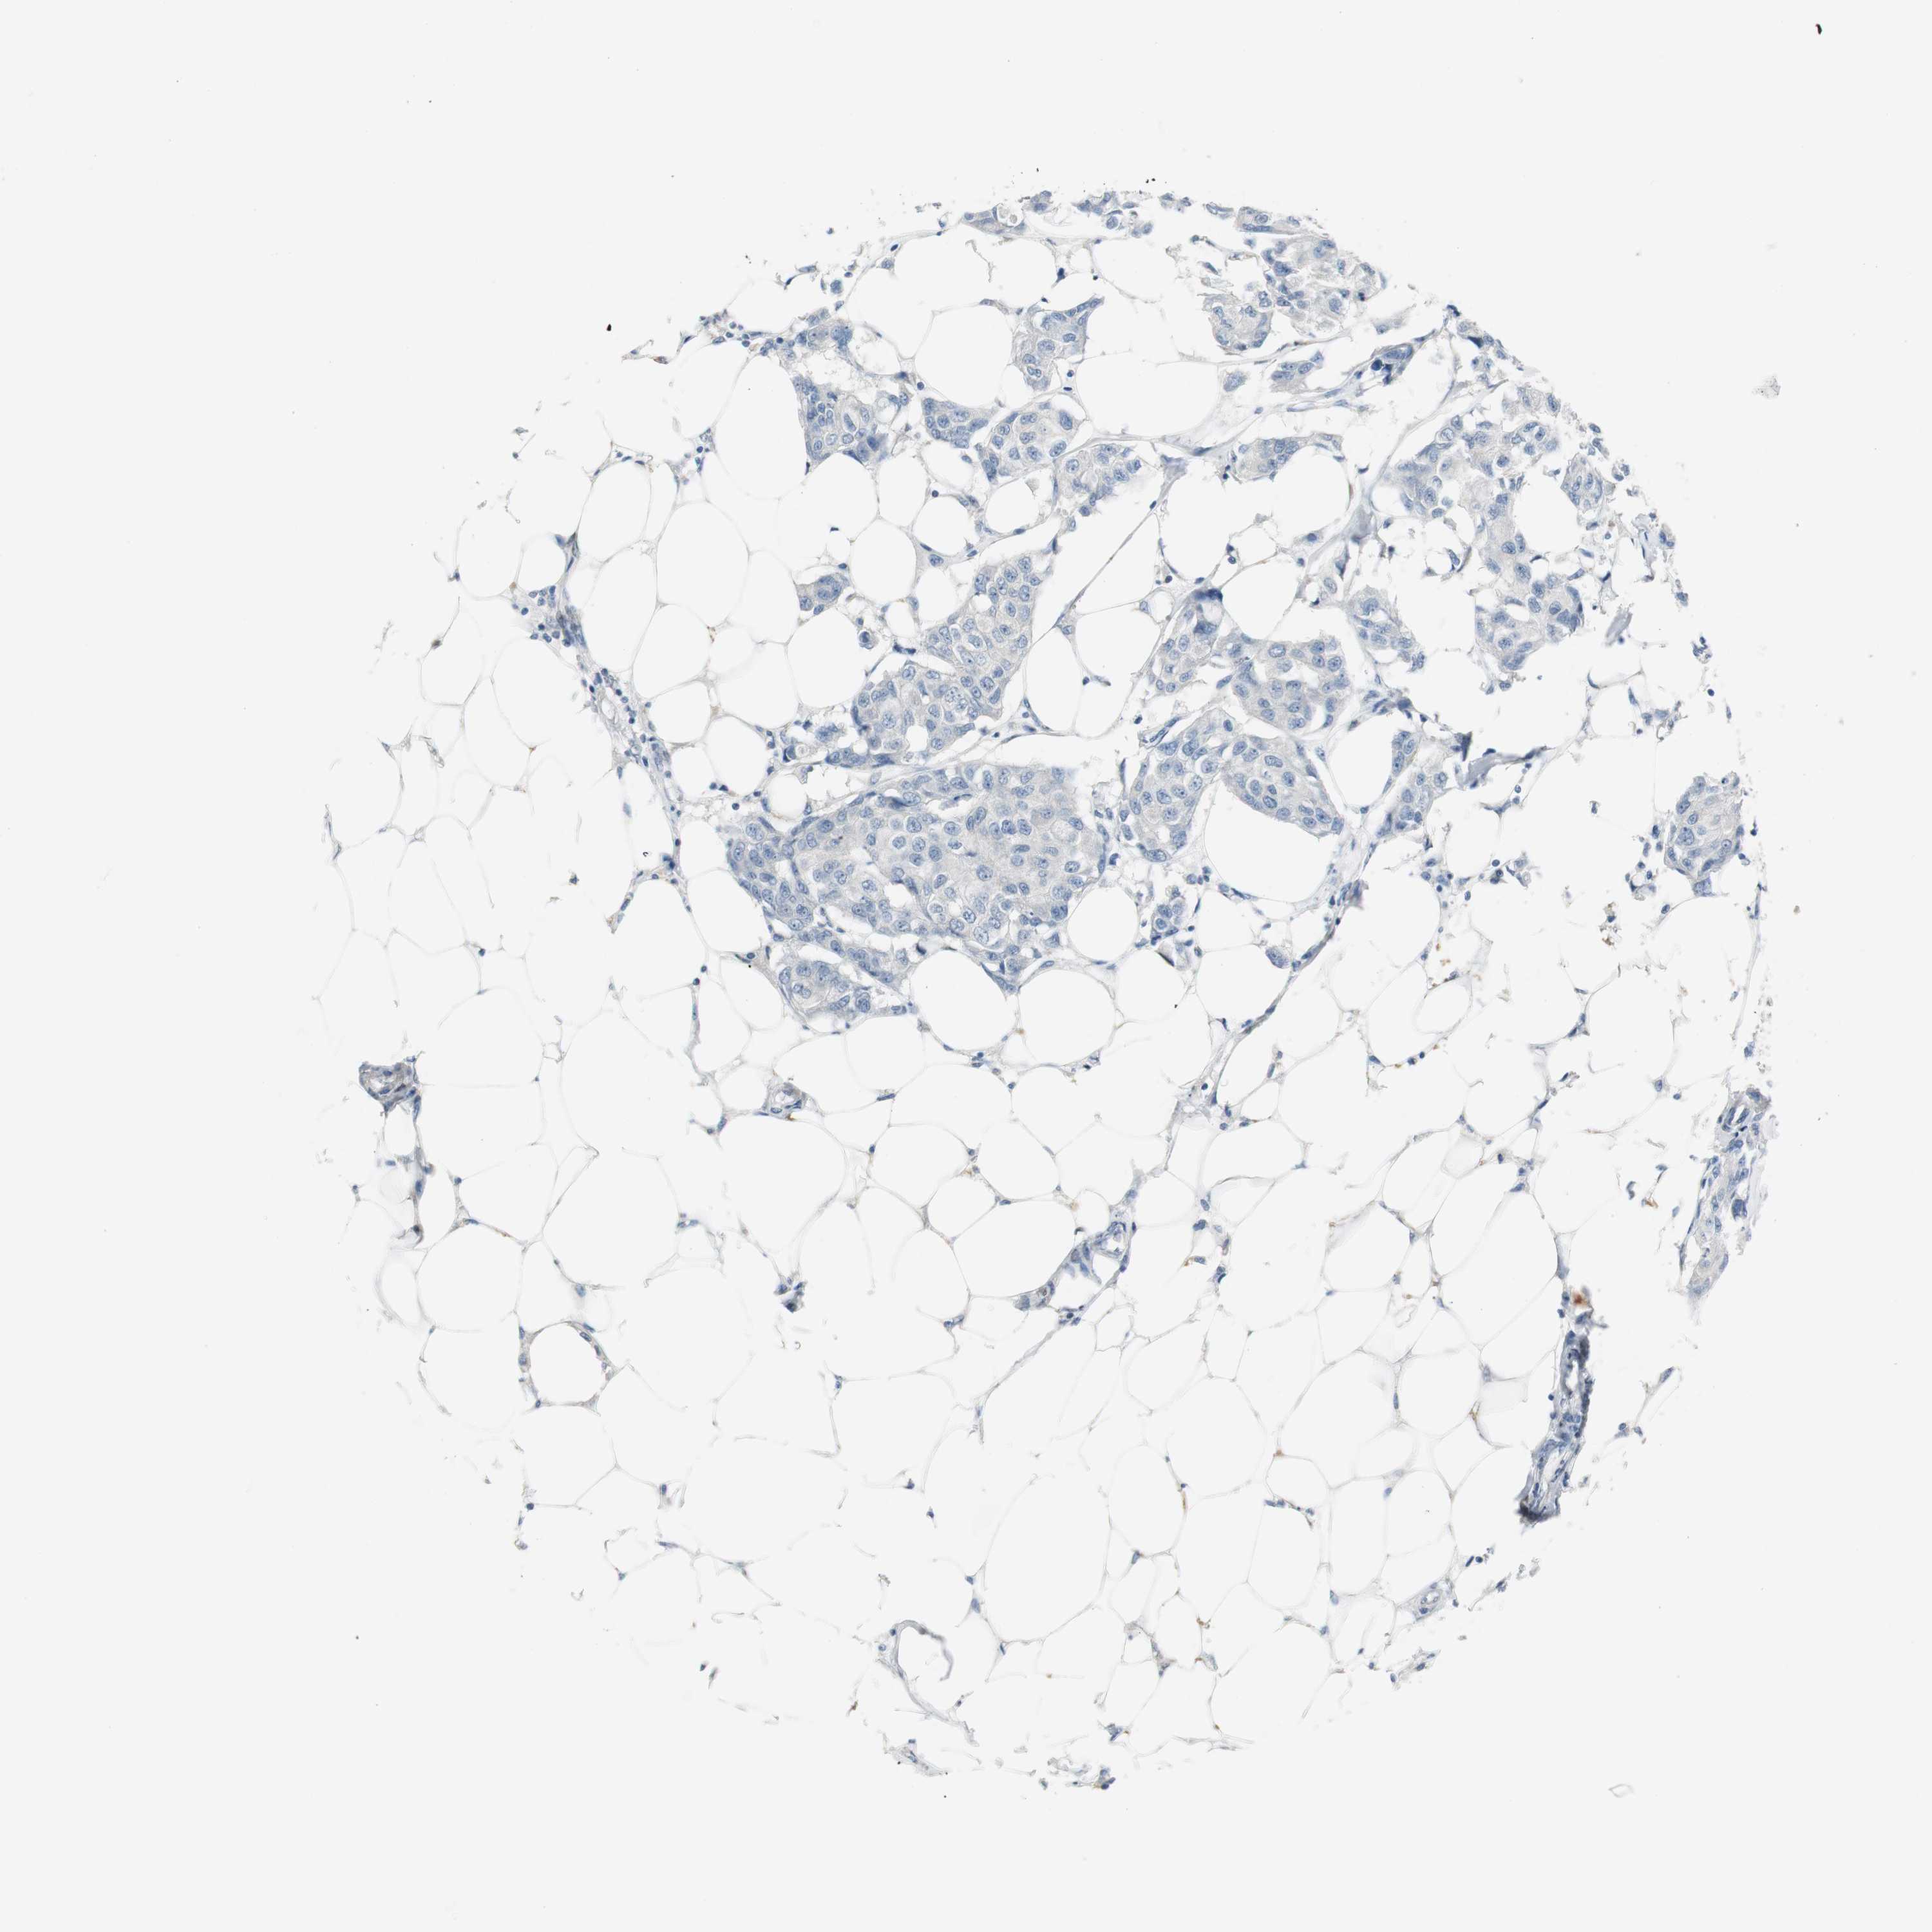

CANCER BREAST CANCER Show tissue menu

BRCA TCGA BRCA VALIDATION PROTEIN EXPRESSION

Breast cancer

Human cancer